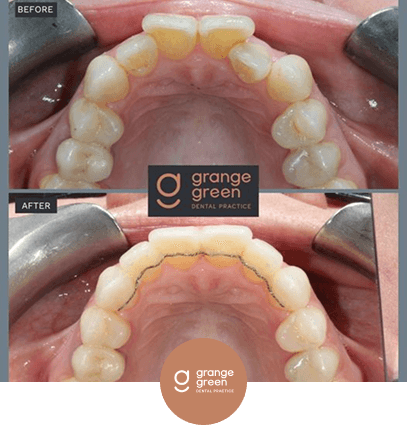

Here are just a few before and after cases to give you an idea of how we help to transform your smile and your confidence using treatments like orthodontics, bridges, veneers and composite fillings…